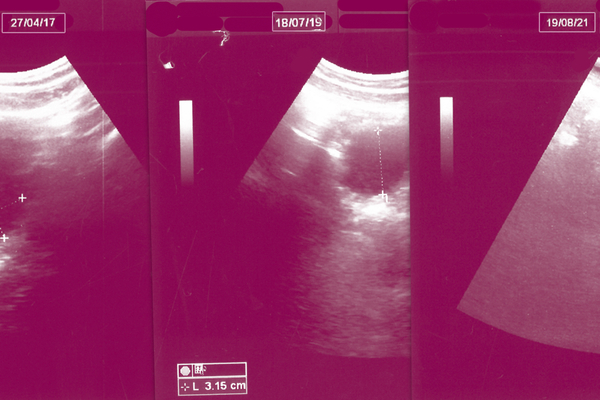

كان الكشف الأول عبارةً عن أسئلةٍ عن انتظام الدورة الشهرية وعمّا إذا كانت تربطني بزوجي قرابة، بما أنّ زواج القربى عادةٌ مُنتشرةٌ في الصعيد تؤدّي أحيانًا إلى ولادة أطفالٍ مصابين بالتشوّه الخلقي. اطمئنّ الطبيب بجهاز السونار على شكل الرحم وحجم البويضة ومدى نشاطها بمساعدة فتاةٍ تقف بجواره لتساعد النساء في رفع ملابسهنّ ووضع السائل اللزج على بطونهنّ كي يمرّر الطبيبُ جهازه فوق منطقة الرحم ويرى في شاشةٍ بائسةٍ شخبطاتٍ سوداء وبيضاء ترسم شكل الرحم. بعد انتهائه من الكشف، كتب لي بعض الأدوية المُنشّطة للبويضة والفيتامينات، وكذلك لزوجي، وطلب منه إجراء تحليلٍ للسائل المنوي، كما طلب منّا المتابعة معه مرةً كلّ شهر، مشيرًا إلى أن الحمل قد يحصل في أيّ وقتٍ طالما ألّا وجود لأيّ موانع طبيةٍ أو نفسية.

تكرّرت الزيارات على مدى سبعة أشهر، قابلتُ فيها نساءً عديداتٍ كان لكلٍّ منهنّ حكاية تسردها في انتظار موعدٍ قد يطول لساعاتٍ عدّة. كانت أعمارهنّ مختلفة، فهناك من تجاوزَت الأربعين وتجرّ أطفالها معها وفي بطنها جنينٌ آخر، وهناك من لا تزال عروسًا حملَت بعد شهرٍ من زواجها ولم تتجاوز بعد سنّ الثامنة عشر. كما كان هناك من تمنّي النفس بطفلٍ منذ سنين، فتروح وتجيء إلى عيادات الأطباء. وعلى الرغم من أن غالبية المريضات كنّ من الريف، كان الطبيب يقسم أيام الكشف بين عيادات القرى والمدينة نظرًا لبُعد بعض القرى عن المدينة وصعوبة تنقّل بعض النساء. ففي العادة، تلجأ النساء إلى المتابعة مع طبيبٍ أو طبيبةٍ في عيادةٍ خاصةٍ حتّى لو اضطُررن للسفر إلى المدينة، حيث توجد مستوياتٌ عدةٌ من العيادات الخاصّة مقسّمةٌ وفق الإمكانات المادية، إذ لا توجد رعايةٌ صحيّةٌ مخصّصةٌ للحوامل أو الراغبات في الحمل في الوحدات التابعة لوزارة الصحة.